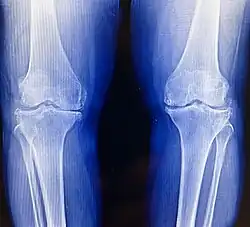

Imaging tests like X-rays are commonly utilized to diagnose and monitor arthritis.[61] Other imaging tests for rheumatoid arthritis that may be considered include computed tomography (CT) scanning, positron emission tomography (PET) scanning, bone scanning, and dual-energy X-ray absorptiometry (DEXA).[61]

Osteoarthritis

Bilateral medial joint space narrowing with osteophytes in varus knees with osteoarthritis

Osteoarthritis (OA) is the most common form of arthritis.[62] It affects humans and other animals, notably dogs, but also occurs in cats and horses. It can affect both the larger (i.e. knee, hip, shoulder, etc.) and the smaller joints (i.e. fingers, toes, foot, etc.) of the body. The disease is caused by daily wear and tear of the joint. This process can progress more rapidly as a result of injury to the joint. Osteoarthritis is caused by the break down of the smooth surface between two bones, known as cartilage, which can eventually lead to the two opposing bones coming in direct contact and eroding one another. OA symptoms typically begin with minor pain during physical activity, but can eventually progress to be present at rest. The pain can be debilitating and prevent one from doing activities that they would normally do as part of their daily routine. OA typically affects the weight-bearing joints, such as the back, knee and hip due to the mechanical nature of this disease process. Unlike rheumatoid arthritis, osteoarthritis is most commonly a disease of the elderly. The strongest predictor of osteoarthritis is increased age, likely due to the declining ability of chondrocytes to maintain the structural integrity of cartilage.[63] More than 30 percent of women have some degree of osteoarthritis by age 65. One of the primary tools for diagnosing OA are X-rays of the joint. Findings on X-ray that are consistent with OA include those with joint space narrowing (due to cartilage breakdown), bone spurs, sclerosis, and bone cysts.[64]